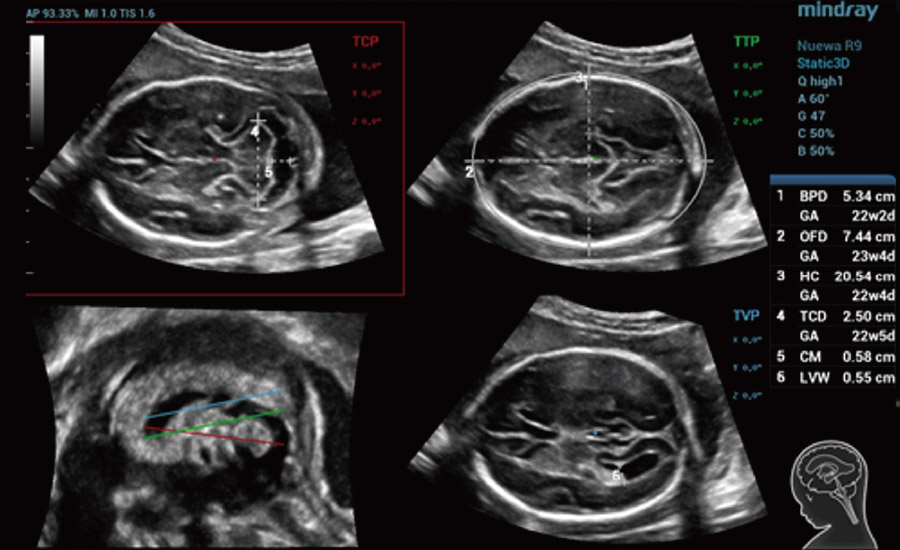

Informa??es abrangentes adaptadas aos cenƔrios

Por meio da combina??o de algoritmos avan?ados e do conhecimento especĆfico da regi?o, a inovadora solu??o Smart Scene permite a identifica??o automĆ”tica das caracterĆsticas do tecido e fornece diagnĆ³stico especĆfico dos Ć³rg?os com informa??es completas. Com base na identifica??o automĆ”tica de cenĆ”rios, a solu??o realiza n?o apenas a varredura 2D inteligente com configura??es e medidas automĆ”ticas, mas tambĆ©m oferece informa??es 3D abrangentes em todas as etapas, desde a otimiza??o de imagens volumĆ©tricas atĆ© a difĆcil obten??o de planos 2D, e a quantifica??o durante todo o procedimento. Ele ajuda a reduzir em grande parte a dependĆŖncia de habilidades clĆnicas, ao mesmo tempo que aumenta a precis?o, a confian?a e a eficiĆŖncia no diagnĆ³stico.

ObstetrĆcia